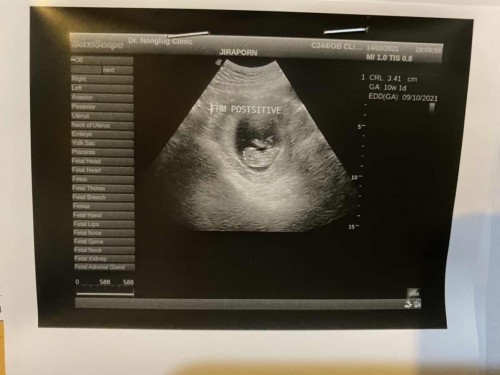

มีแม่ๆท่านไหน หัวปีท้ายปีแล้วเลี้ยงคนเดียวบ้างไหมคะอยากทราบว่าพอจะเลี้ยงคนเดียวไหวไหม ? คนโตพึ่ง11 เดือนมนท้องมา10w5d แล้วค่ะ